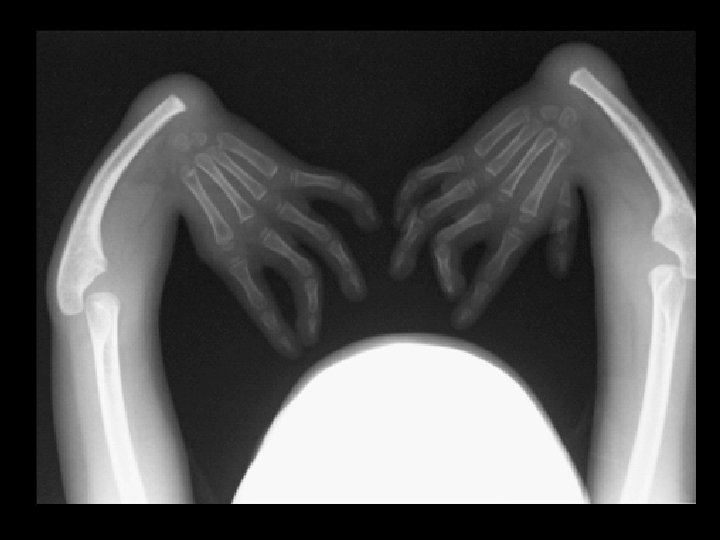

Thrombocytopenia-absent radius syndrome • • Findings: – Absent bilateral radii and left thumb – Prone to bleeding due to thrombocytopenia ddx: – Many other causes of radial dysplasia • Holt Oram • VATER • Fanconi syndrome